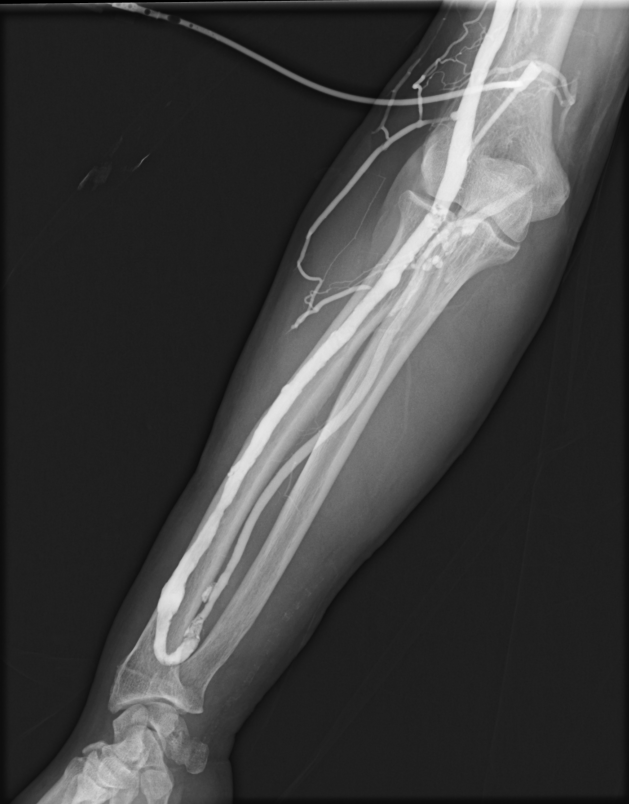

血管撮影装置

当院は令和6年3月の新病院発足に伴い、より高精度で安全な検査・血管内治療(IVR:Interventional Radiology)を提供するため最新の島津製作所製バイプレーンシステムTrinias B12s(Opera smart)を導入しました。

平面型X線検出器(FPD:Flat Panel Detector)を搭載し、カテーテルを用いた高度な血管内治療においてより少ないX線で高い解像度の画像を描出可能となりました。

バイプレーンシステムを採用したことにより、一回の造影剤注入で2方向撮影が可能となり、従来のシングルプレーンと比較して造影剤使用量を半分程度に抑えることができ、被ばくを低減すると共に検査時間の短縮にも繋がり、より患者さまの負担を軽減することが可能となりました。

冠動脈造影検査(CAG:Coronary Angiography)をはじめ、経皮的冠動脈インターベンション(PCI:Percutaneous Coronary Intervention)、下肢動脈のインターベンション(EVT:Endovascular Treatment)、肝動脈化学塞栓術(TACE:Transcatheter Arterial Chemo-Embolization)等、心血管領域、腹部血管領域における高度なカテーテル治療においてその性能を発揮しております。